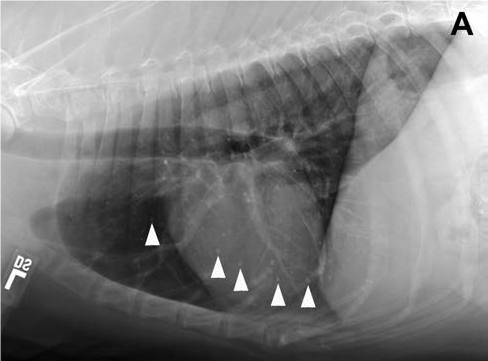

This radiograph is from a 15 year old, male neutered, mixed-breed dog. The arrows are pointing to multifocal, well-defined, 1- to 3.5-mm-diameter mineral opacities. These represent pulmonary osteomas, a common finding in clinically normal older dogs. The development of these nodules involves a change in differentiation from one cell type to another. This is an example of _______ and these would be considered a(n) _____________.

Metaplasia, incidental lesion